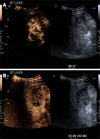

Improvements in imaging technology allow exploitation of the dual blood supply of the liver to aid in the identification and characterisation of both malignant and benign liver lesions. Imaging techniques available include contrast enhanced ultrasound, computed tomography and magnetic resonance imaging. This review discusses the application of several imaging techniques in the diagnosis and staging of both hepatocellular carcinoma and cholangiocarcinoma and outlines certain characteristics of benign liver lesions. The advantages of each imaging technique are highlighted, while underscoring the potential pitfalls and limitations of each imaging modality.